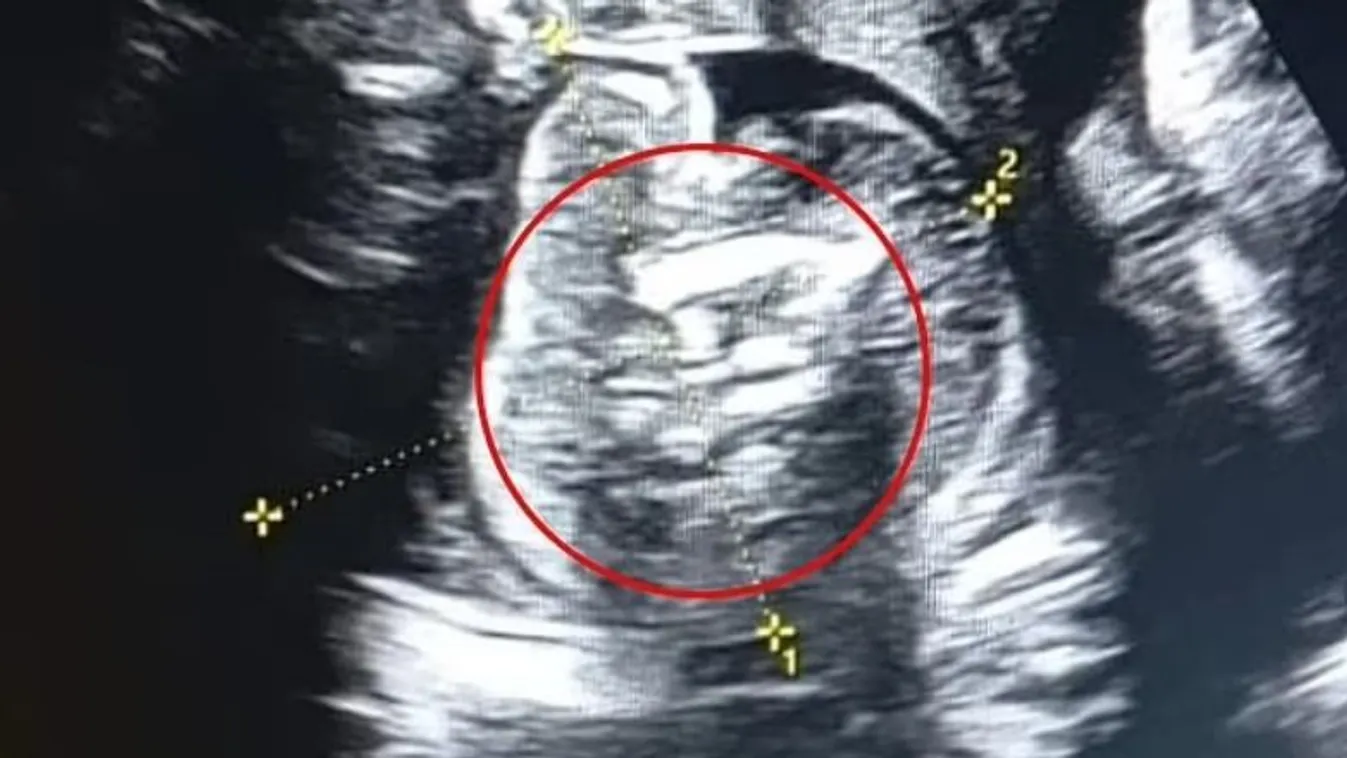

Az orvosok teljesen ledöbbentek az ultrahang láttán.